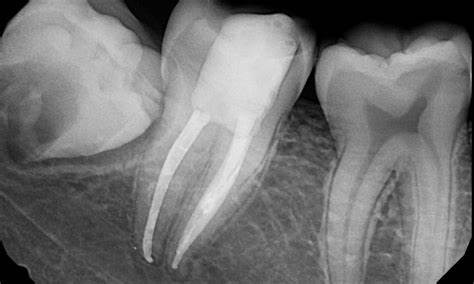

Our teeth, just like any other part of our body is also supplied by nerves and blood vessels. Its called the PULP of the tooth. And just like any other part of the body, it carries a risk of being diseased or infected.

Superficial infections or caries as we dentists call it still have a bright chance of being treated by normal tooth fillings. But many times patients report to us with lots of pain and strong sensitivity in teeth.

That is simply because the infection had reached the Pulp of the tooth and we have ignored the tooth for a long time.